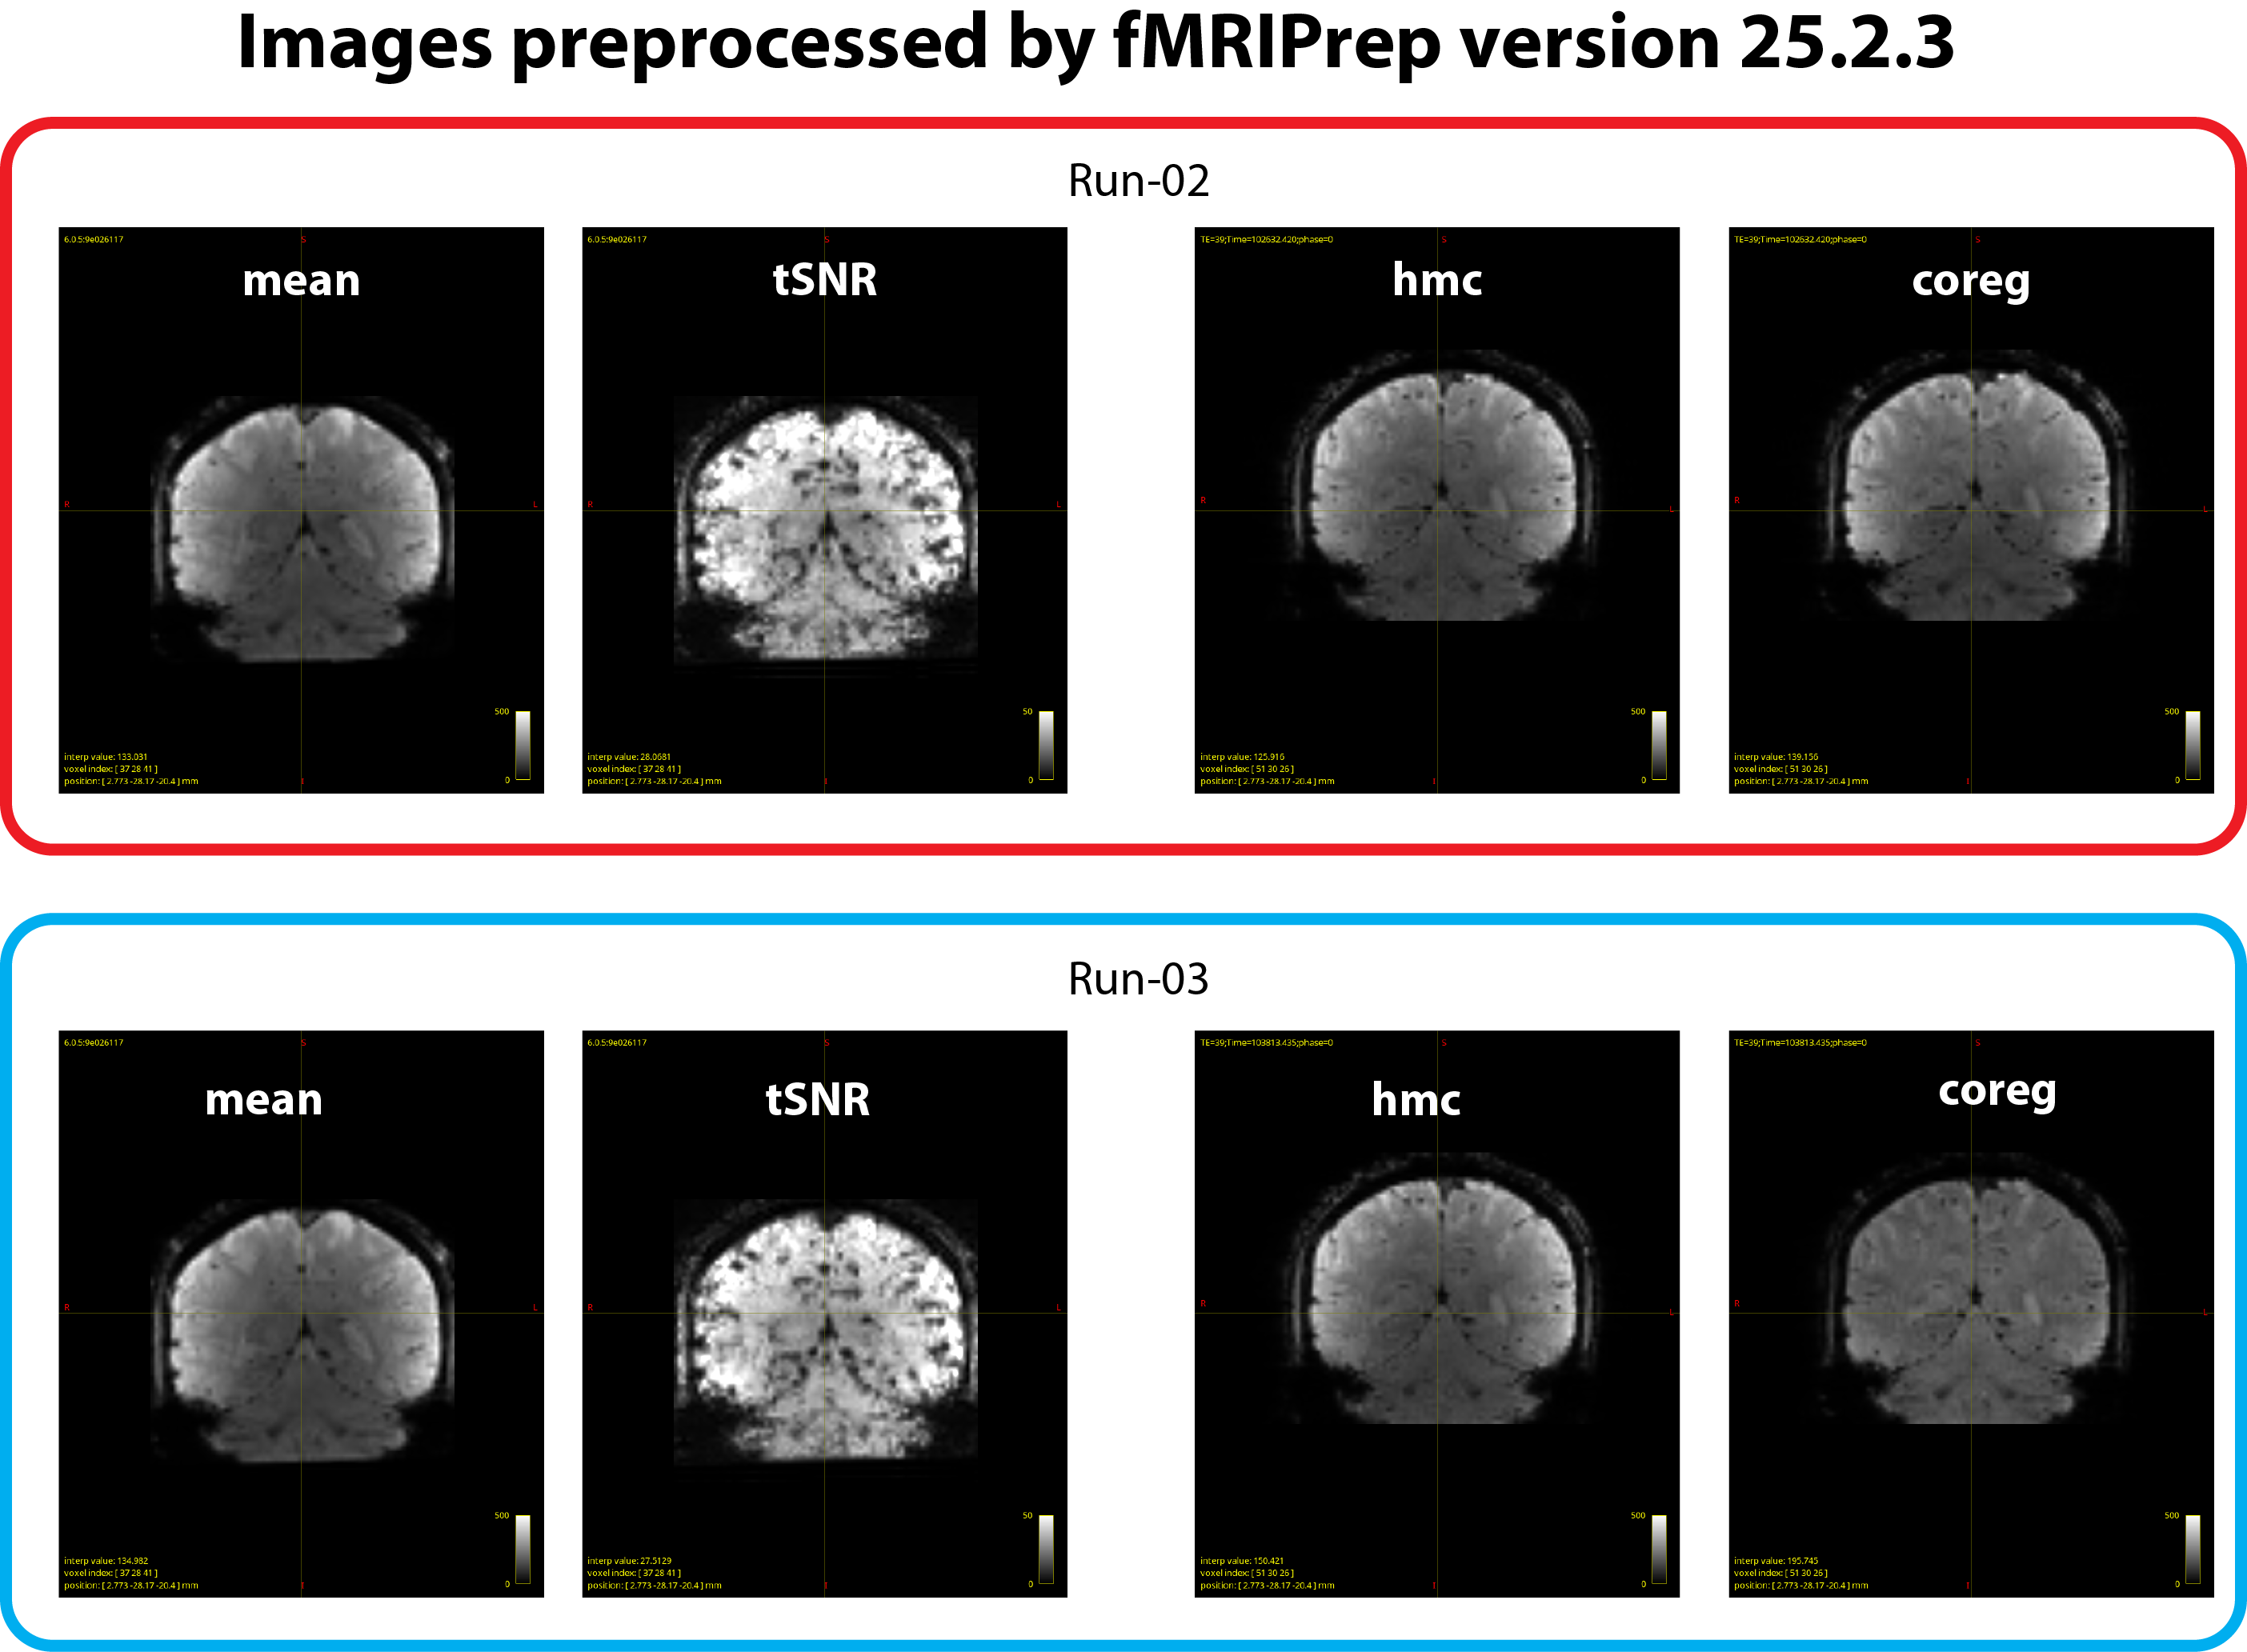

We suspected whether updating the fMRIPrep version would help. When we rerun the same analysis using ver 25.2.3, we found that a degree of inter-run inconsistency in *_desc-coreg_boldref.nii.gz images became much less compared with output from ver 24.1.1. However, perhaps some of the differences may still exist in this case, although it looks much better (see figure 3 below).